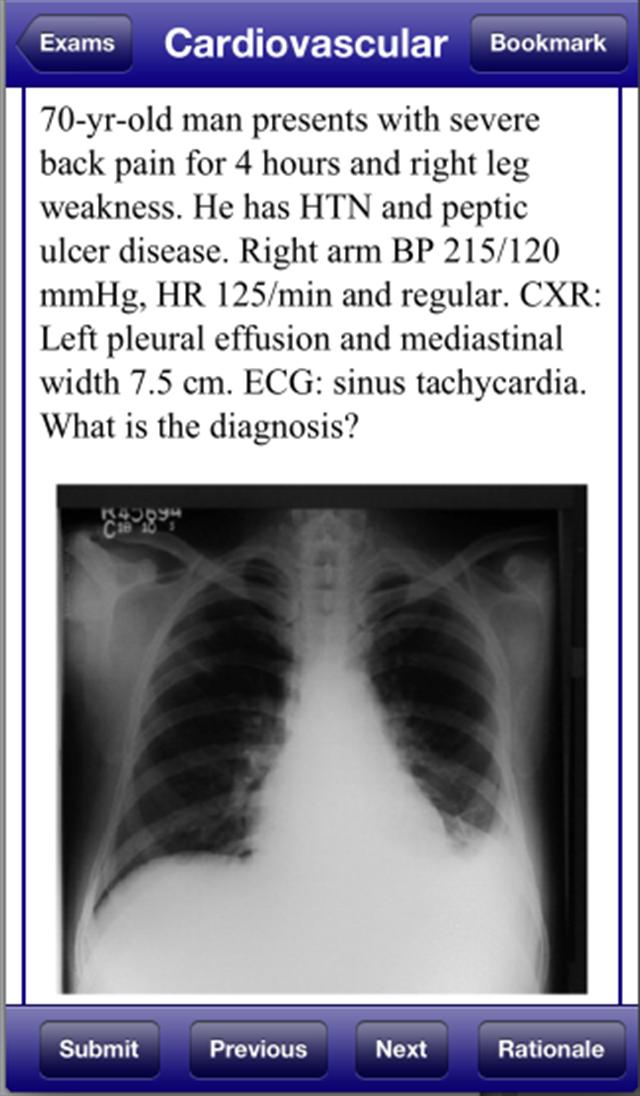

USMLE 2 Stanford Review Course, by David Nobel, MD, replicates the actual USMLE Step 2 Clinical Knowledge examination. USMLE 2 Stanford Review Course includes 1800 questions and answers written by trusted medical school professors who have reviewed the most recent USMLE 2 examination. USMLE 2 Stanford Review Course also includes 300 image format questions, including CT scans, MRIs, ECGs, and dermatology pictures.